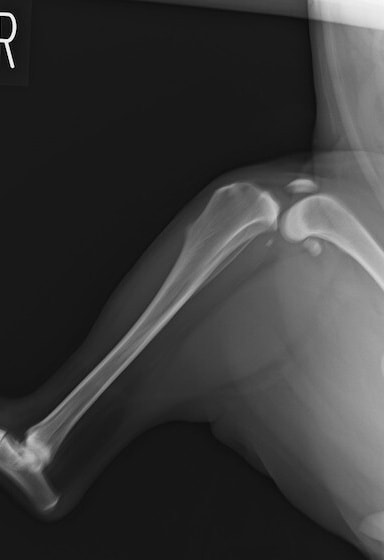

術前左後肢側面像

左後肢の挙上を主訴に来院されました。触診にて両関節の前方引き出し兆候、両膝蓋骨の内方脱臼を認めました。関節液検査より免疫介在性多発性関節炎は否定的でした。レントゲン検査にてfat pad signを伴う関節炎が認められたことから、前十字靭帯断裂と膝蓋骨内方脱臼(左GradeⅢ 右GradeⅢ〜IV)併発と診断し、手術を行いました。